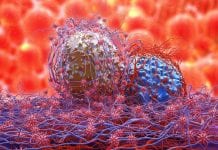

What do you know about immune checkpoint inhibitors?

Immune checkpoint inhibitors have become important tools for managing non-small-cell lung cancer (NSCLC), could the analysis identify individuals with malignant diseases?

Reported in The Journal...